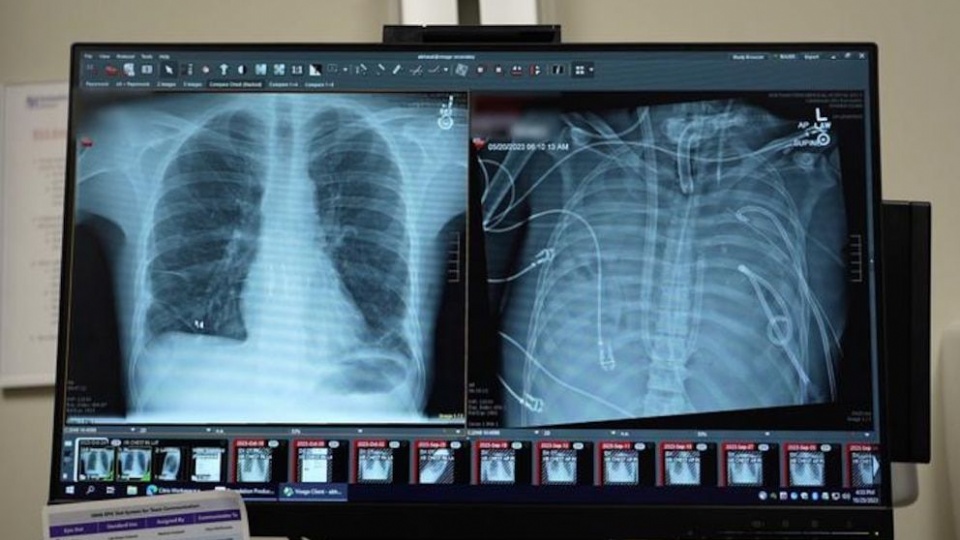

Un hombre con insuficiencia pulmonar severa sobrevivió 48 horas sin pulmones propios, sostenido por un sistema pulmonar artificial completo que oxigenó su sangre y lo mantuvo estable hasta recibir un trasplante exitoso.

Chicago, Estados Unidos. Un hombre con daño pulmonar irreversible logró sobrevivir 48 horas sin pulmones naturales gracias a un pulmón artificial total, un dispositivo experimental que reemplazó por completo la función respiratoria hasta que pudo recibir un trasplante doble de pulmón en un centro médico de alta complejidad.

El pulmón artificial total funcionó como un reemplazo completo de los órganos respiratorios, oxigenando la sangre y eliminando dióxido de carbono sin necesidad de tejido pulmonar. Durante más de 48 horas, el sistema mantuvo al paciente estable, con parámetros fisiológicos compatibles con la vida, mientras se aguardaba la aparición de órganos compatibles para el trasplante.

A diferencia de otras técnicas como la oxigenación por membrana extracorpórea (ECMO) -que solo asisten parcialmente la función respiratoria-, este dispositivo asumió el 100% del trabajo pulmonar, permitiendo que el corazón continuara bombeando sangre oxigenada de forma eficaz.